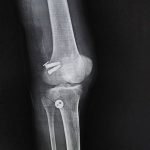

Orthopaedic Surgeon | Arthroscopy & Joint Replacement Specialist

- ACL Reconstruction

- PCL Reconstruction

- Knee Replacement Surgery